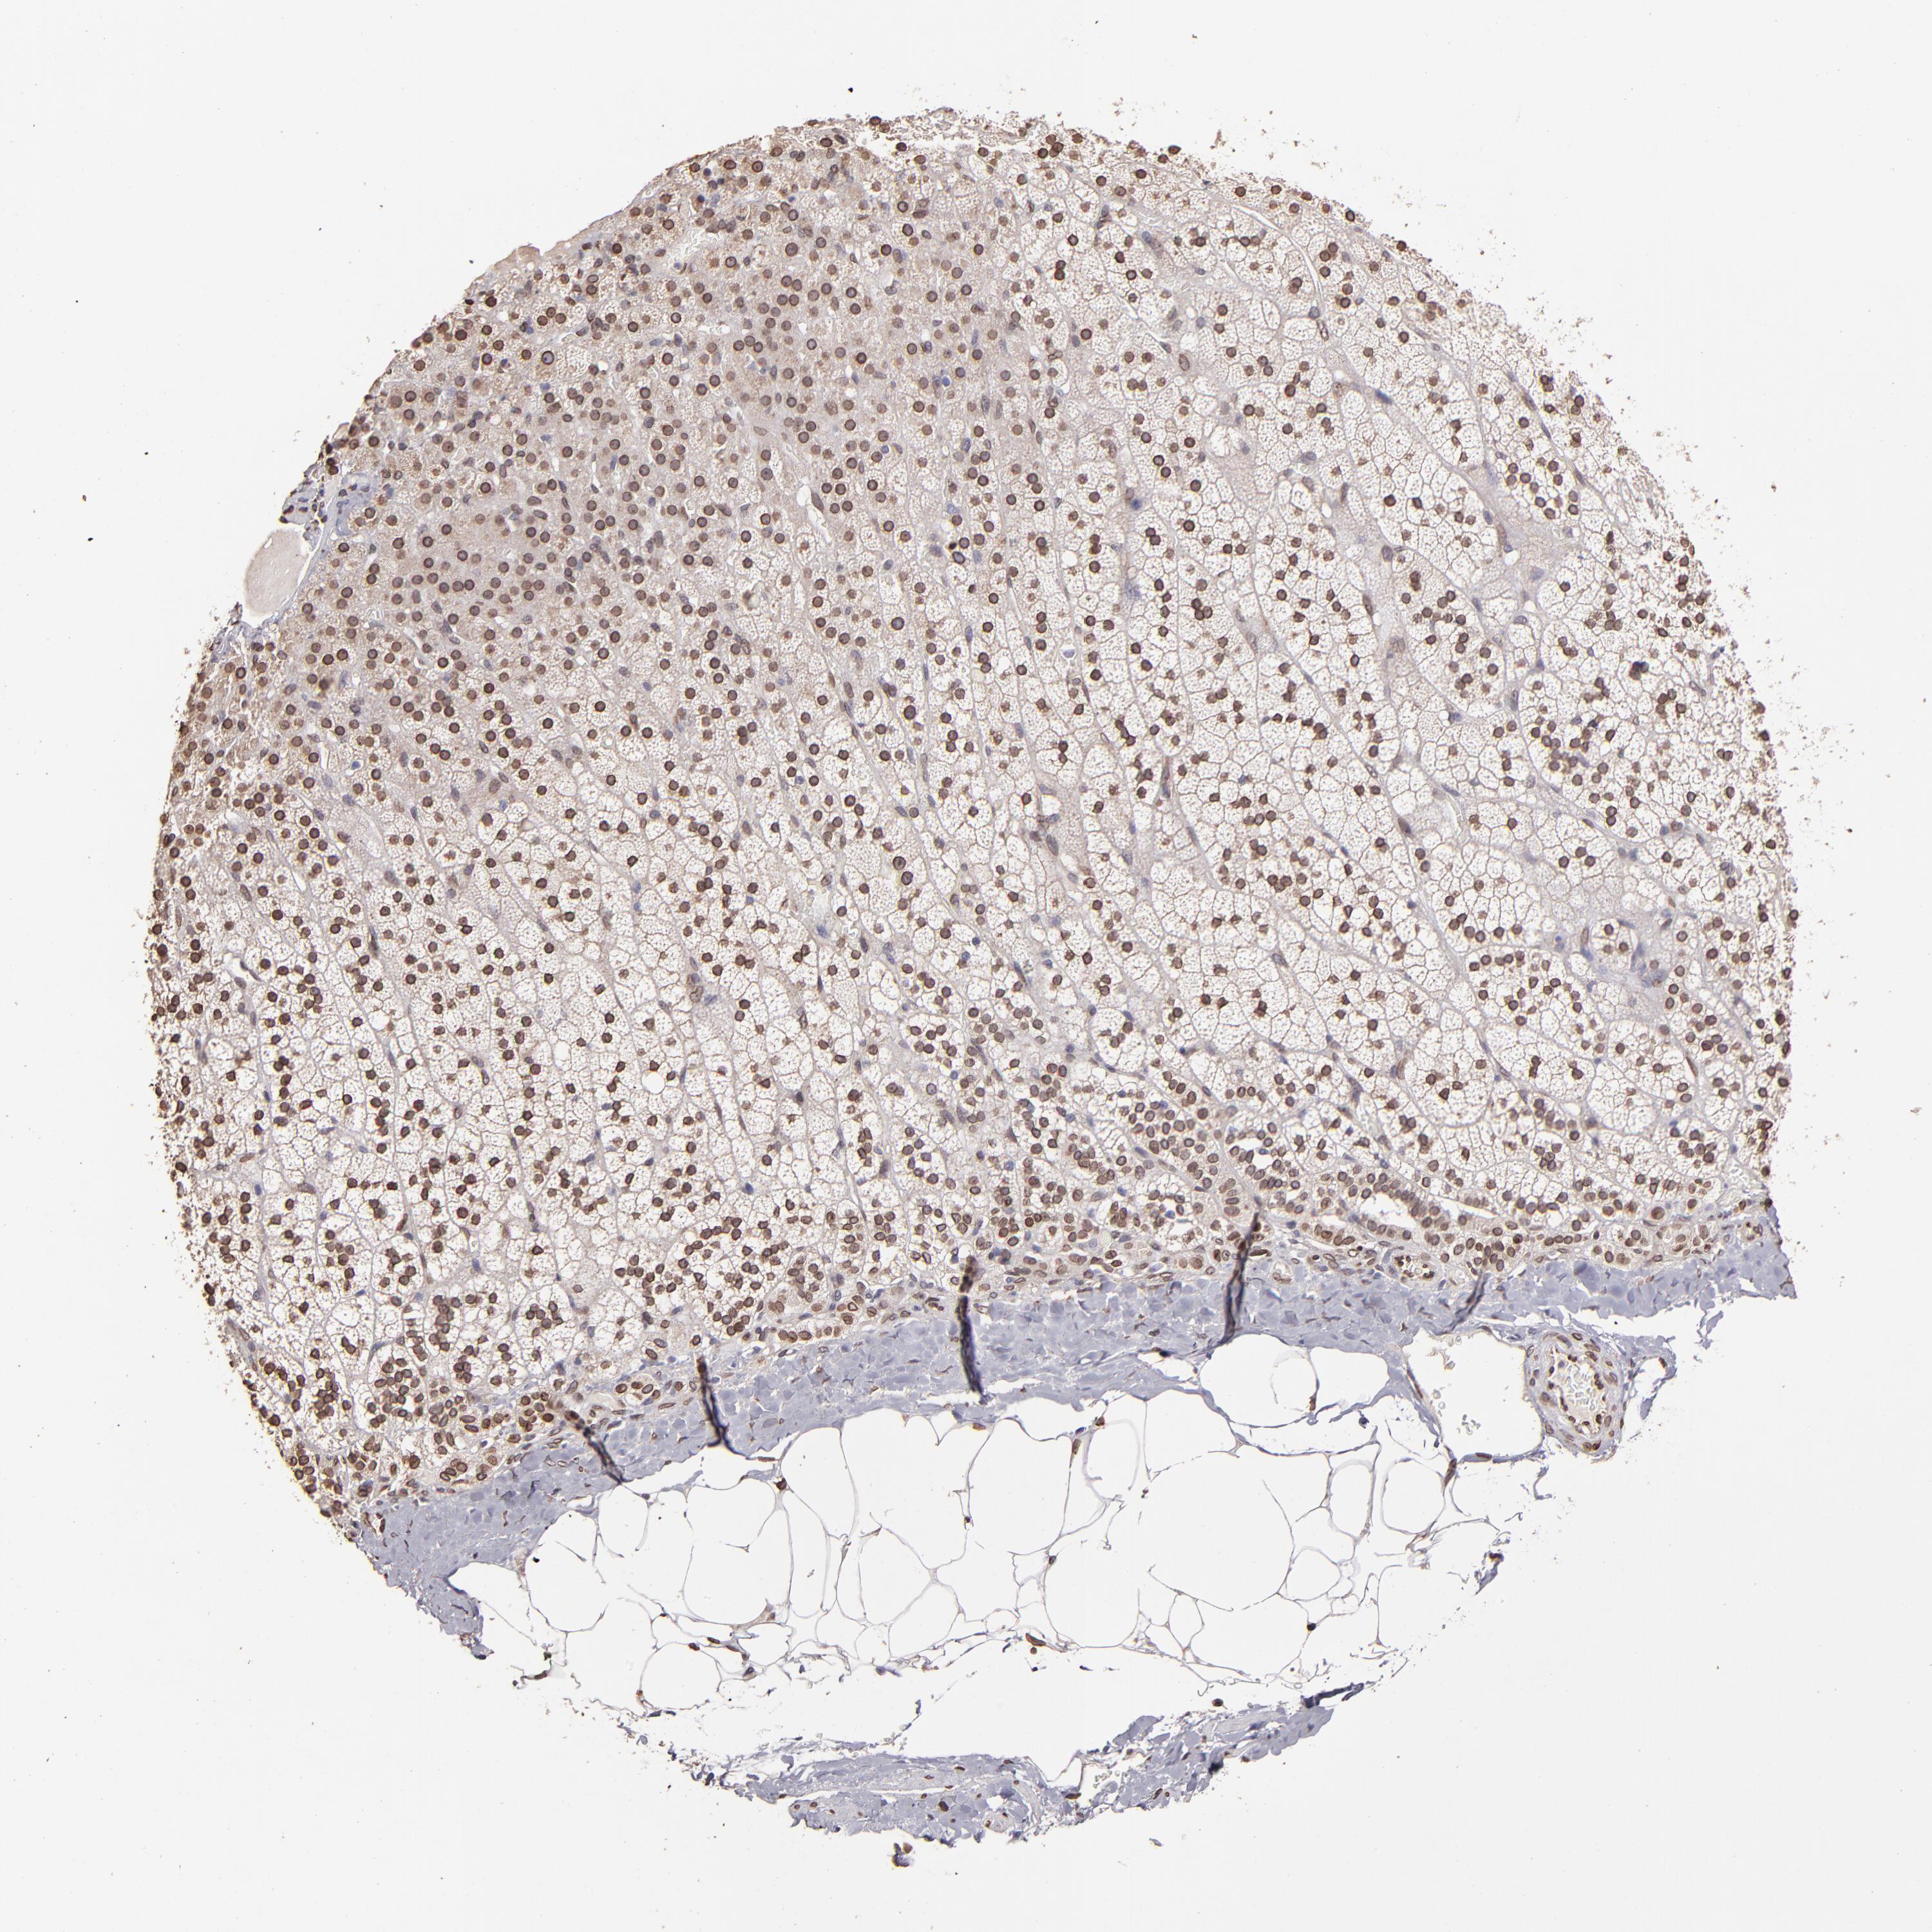

ADRENAL GLAND - Antibody stainingi

Antibody staining in the annotated cell types in the current human tissue is reported as not detected, low, medium, or high, based on conventional immunohistochemistry profiling in selected tissues. This score is based on the combination of the staining intensity and fraction of stained cells.

Each image is clickable and will lead to virtual microscopy that enables deeper exploration of all samples and also displays staining intensity scores, fraction scores and subcellular localization as well as patient and tissue information for each sample.

Antibody HPA002353

Glandular cells Medium